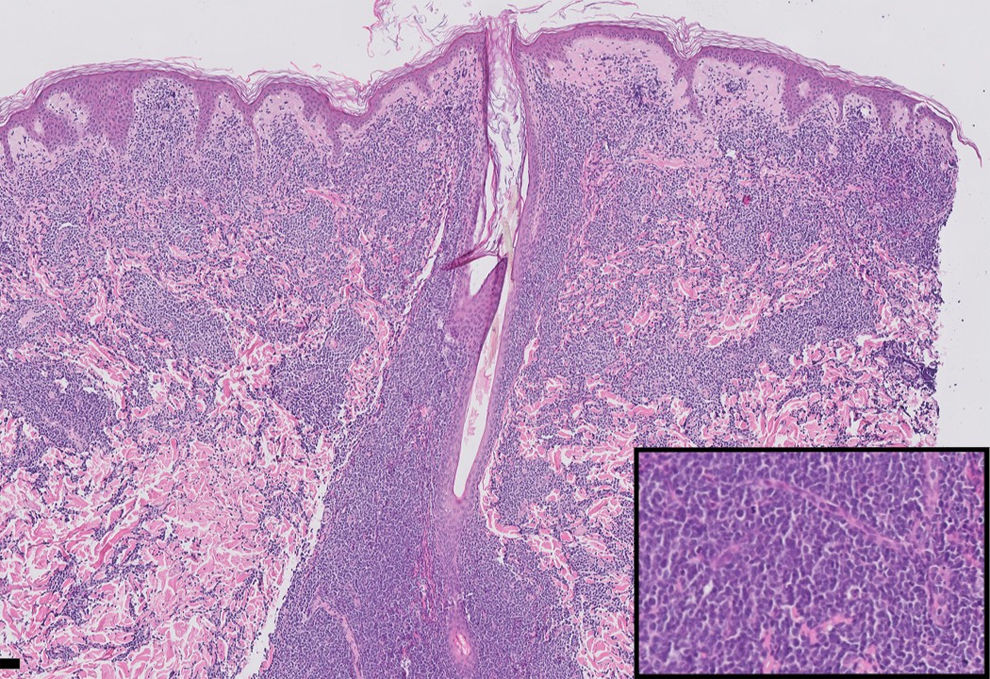

HistopathologyA significant mononuclear cell infiltrate was observed, with a high nuclear-to-cytoplasm ratio and occasional irregular nuclei. The infiltrate extended from the superficial to the deep dermis, with denser concentrations in the papillary dermis and surrounding adnexal structures, without epidermotropism. Cell morphology is detailed in the lower right quadrant (Fig. 2).